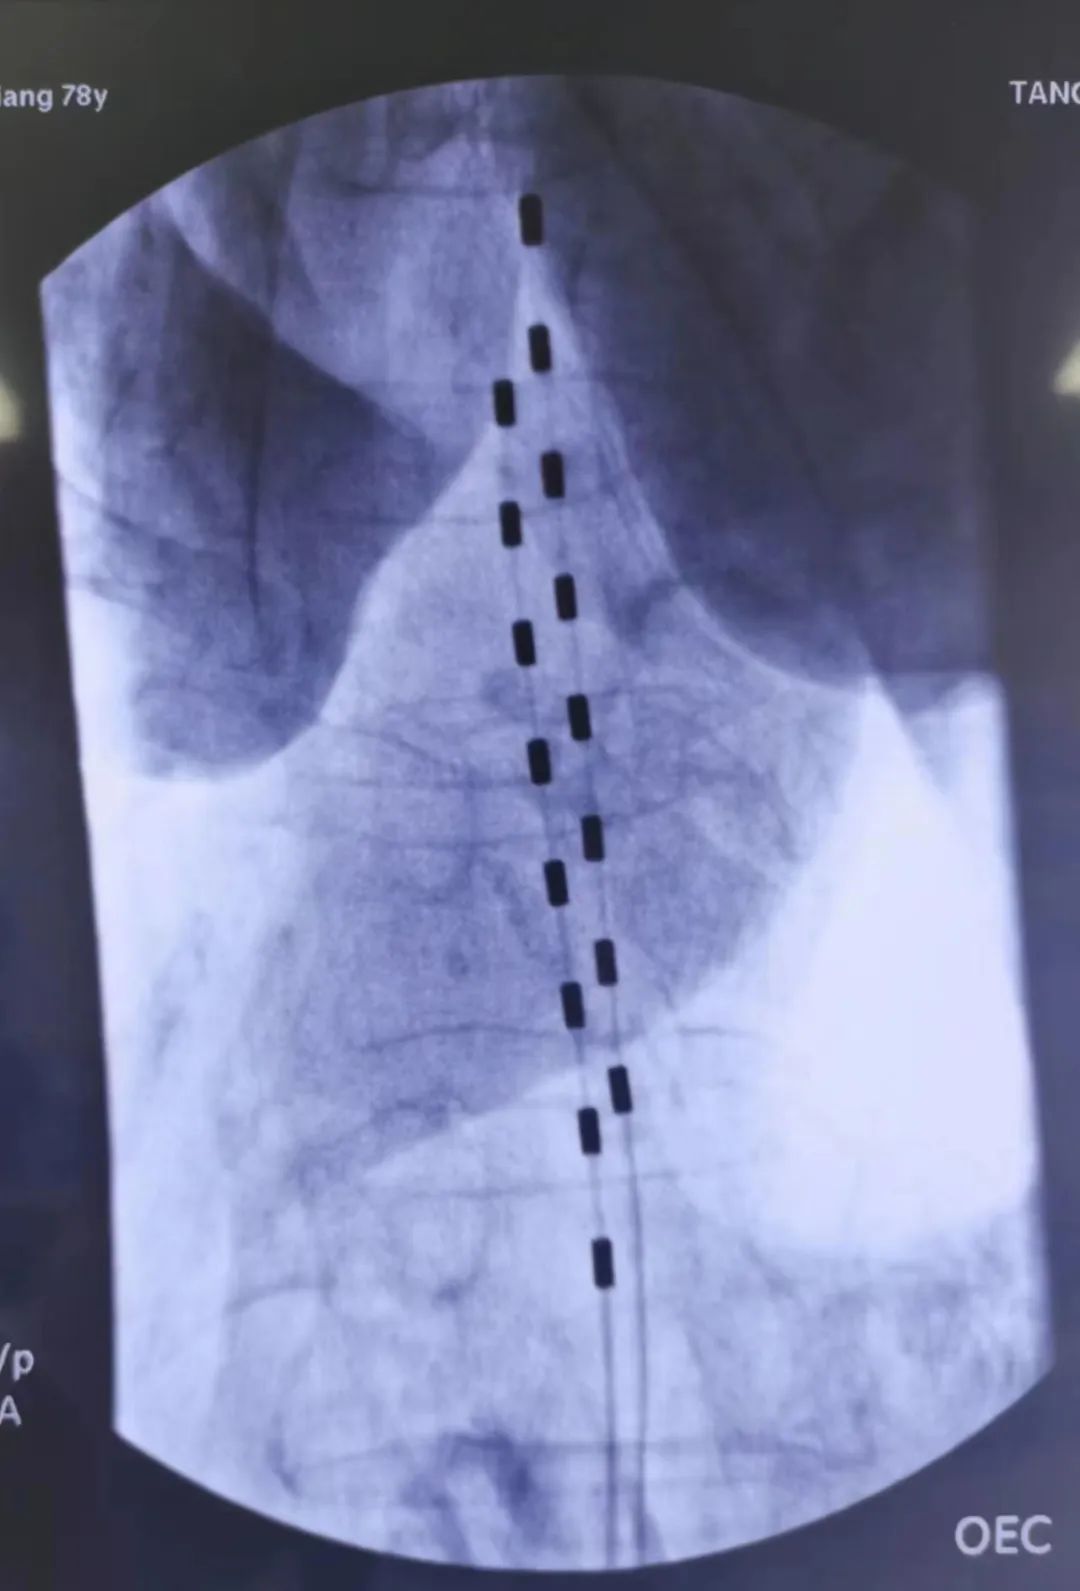

经穿刺针置入导丝引导,置入导管及鞘管、引导电极植入

植入后电极及神经刺激器位置